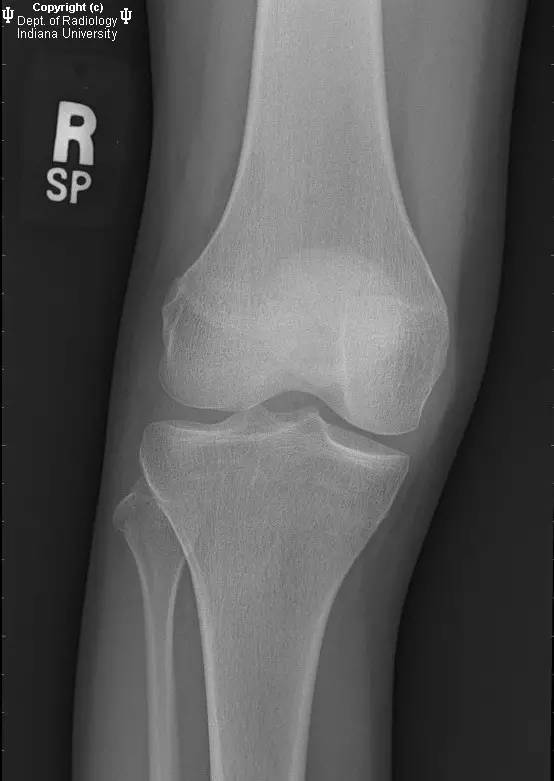

- 膝关节X线:无急性骨折、脱位或半脱位。关节间隙良好。无关节积液。

【诊断】缺血性坏死(AVN)及骨梗死

AVN and bone infarcts

- X片骨梗死示松质骨内不规则或匐行性边界的病变。AVN表现为弧形软骨下透亮区,周围可见斑片状骨丢失区。